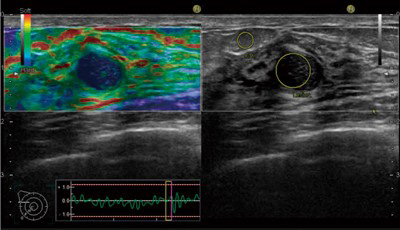

またエコーはエラストグラフィーで腫瘍の硬さを測定し良悪性の判断が容易になりました。